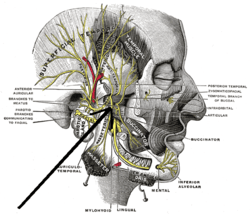

Mandibular division of the trigeminus nerve. (Internal pterygoid nerve visible but not labeled.) | |